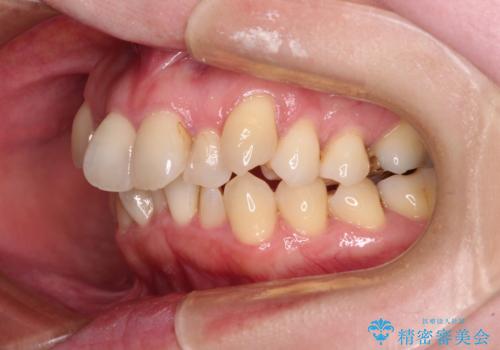

- 上下前歯のデコボコと、上顎の八重歯を気にして来院された患者様です。

下顎に対して上顎が前方にあり、第一大臼歯による咬合状態は上顎前突であったため、上顎のみ左右の第一小臼歯を抜歯し、ワイヤー装置にて矯正治療を行うこととしました。